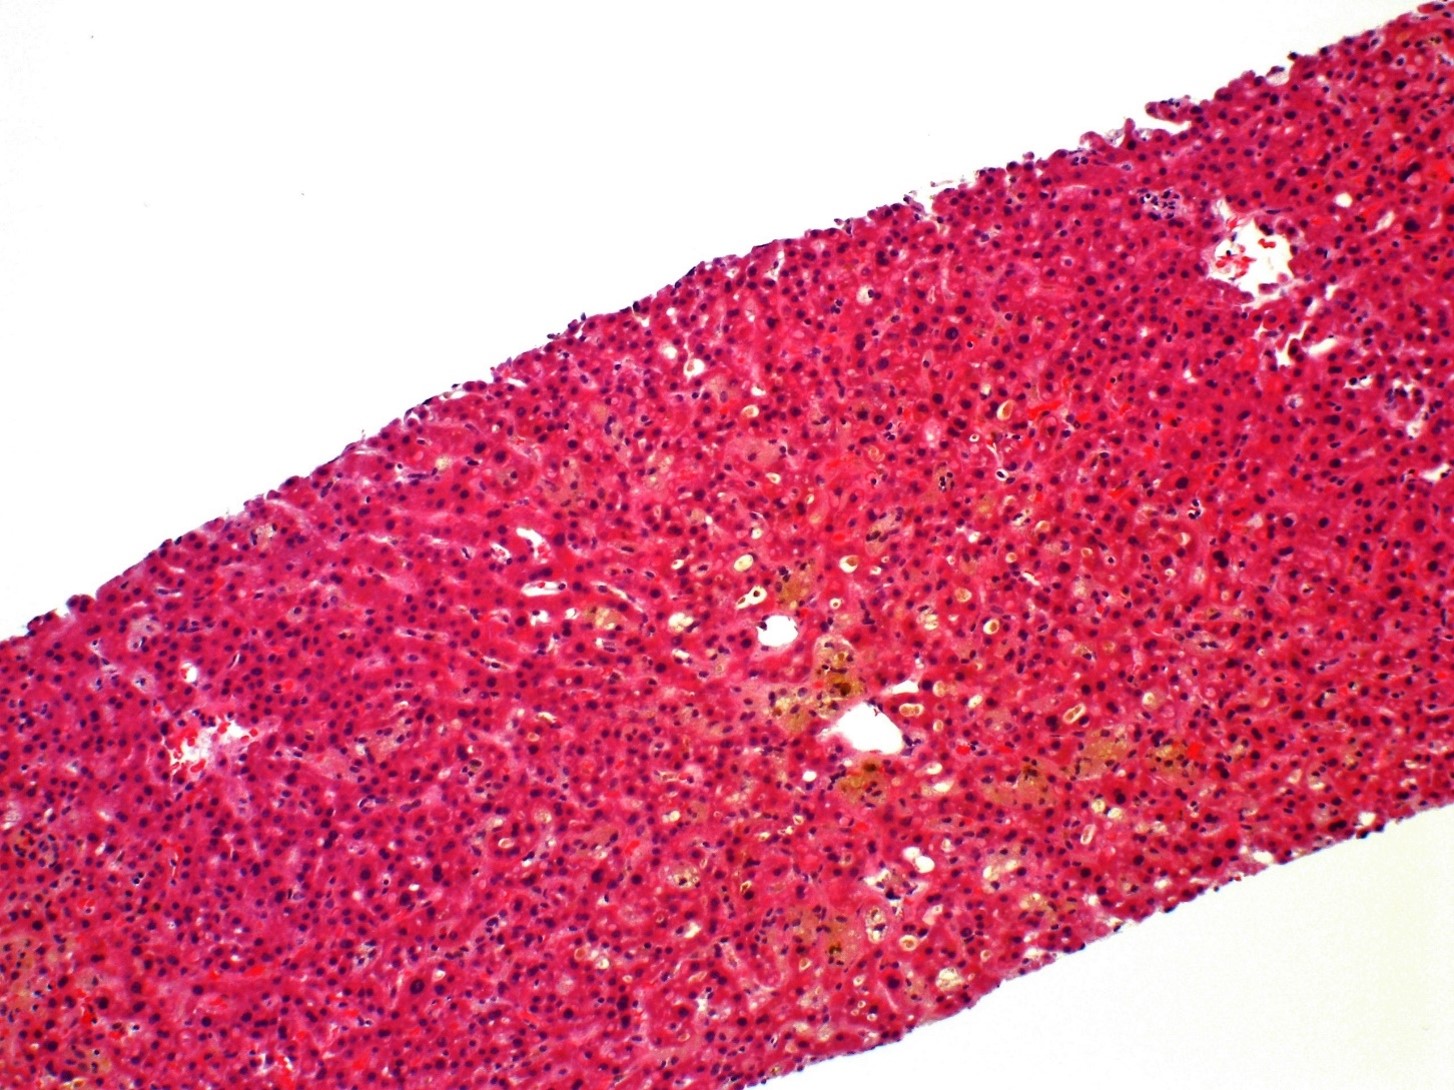

1) A 45-year-old woman described increased fatigue over a period of 1 week and decided to get a doctor’s appointment after her spouse noted scleral icterus. Family history is notable for a maternal aunt with PBC. Her medical history was notable for cholecystectomy 5 months ago and detection of hookworm infection (treated with thiabendazole) 3 weeks prior to this clinic visit. Laboratory studies revealed elevated transaminases and total bilirubin. Liver biopsy revealed bland cholestasis with minimal mixed portal infiltrates. No ductular reaction or granulomatous inflammation were seen. What is her underlying condition?

Answer: B.) Drug-induced liver injury